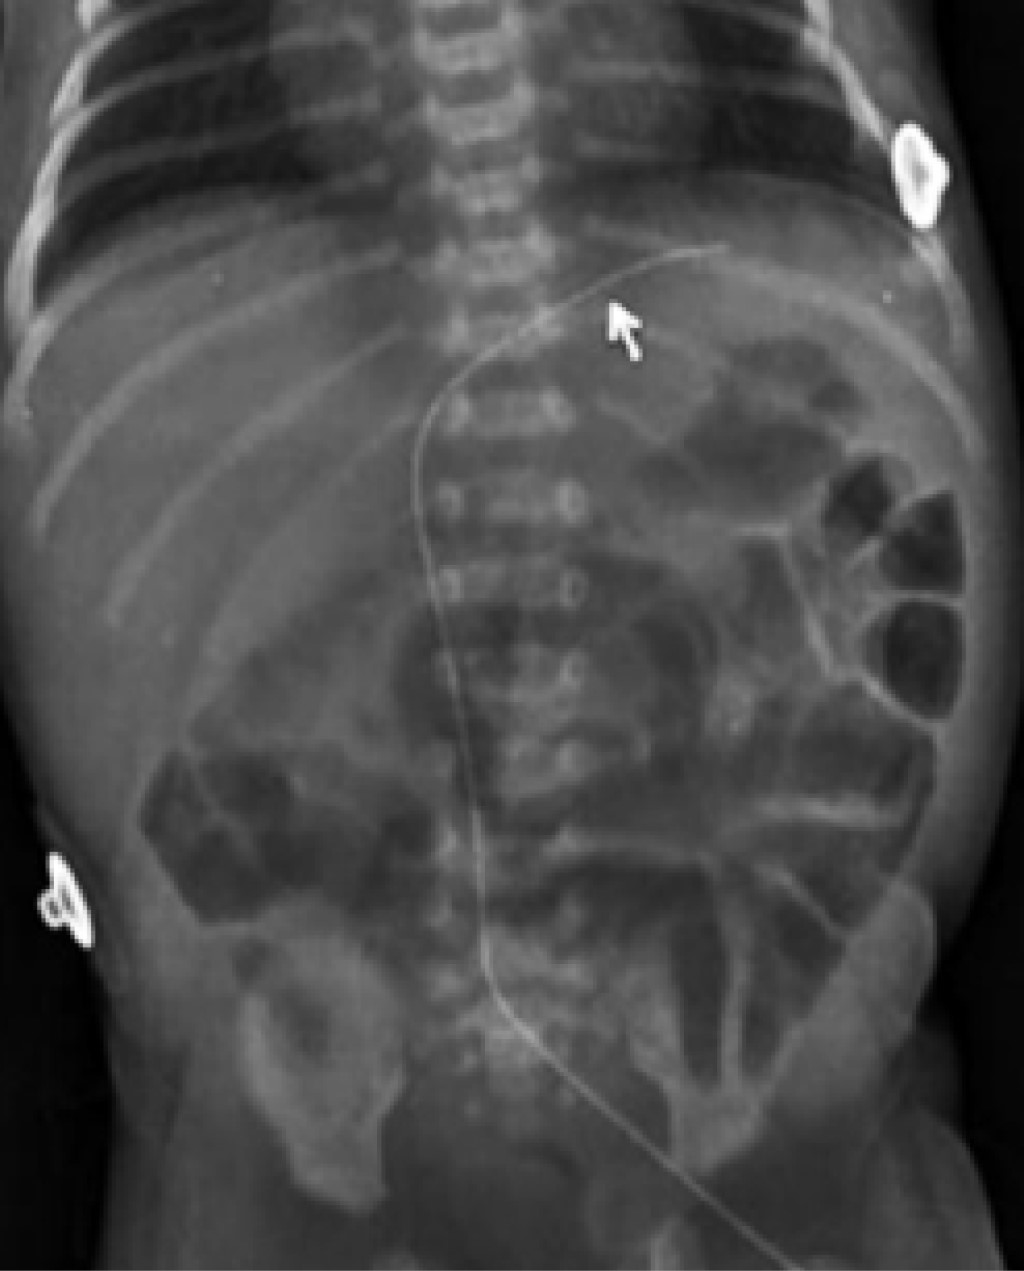

Catéter arterial. La punta del catéter arterial tiene dos posiciones correctas: alta y baja. La posición alta radiológicamente debe quedar entre las vértebras (dorsales o torácicas) D6-9; mientras que la baja entre las vértebras (lumbares) L3-4. De esta manera, se evita la zona peligrosa que queda en el espacio comprendido entre la vértebra dorsal 10 y la vértebra lumbar 2. Esta zona peligrosa comprende el nacimiento de grandes troncos arteriales (tronco celíaco situado en D11, arteria mesentérica superior en D12-L1, arteria renal izquierda y derecha en L1-L2, arterias vertebrales dorsales y lumbares, arteria mesentérica inferior en L3 y bifurcación de la aorta en L4) que deben ser evitados por la posibilidad de provocar la liberación de émbolos o momentos de isquemia que condicionen la aparición de daño renal, intestinal, de médula espinal o de extremidades inferiores (Figuras 7 y 8).2

Una vez conocida la distancia hombro-ombligo, recurrimos al nomograma de Dunn arterial (Figura 3), y seleccionamos en las abscisas esta distancia, enseguida determinamos la altura del catéter, alta o baja. Si seleccionamos la posición alta, situamos la punta del catéter en la mitad de las líneas que delimitan ombligo-diafragma y ombligo-válvula aórtica, y de esta manera se obtiene en las ordenadas la distancia a introducir del catéter arterial alto. Si deseamos colocar la punta del catéter arterial en posición baja, seleccionamos la distancia hombro-ombligo en las abscisas del monograma de Dunn arterial y la punta del catéter lo situamos inmediatamente por arriba de la línea ombligo-bifurcación de la aorta y, de esta manera, determinamos en las ordenadas la distancia a introducir del catéter arterial bajo. Siempre debemos sumar la longitud del muñón umbilical a la distancia obtenida. Antes de fijar y retirar campos estériles solicitamos una radiografía toracoabdominal portátil para determinar la posición de la punta del catéter y si es necesario se hacen modificaciones. Una vez terminado el procedimiento de colocación y posicionamiento del catéter arterial umbilical y de haber retirado el campo estéril no será posible introducir el catéter para tratar de dejar la punta en posición correcta, pero sí se podrá retirar algunos centímetros para posicionarlo correctamente. El trayecto que normalmente debe seguir el catéter arterial es el siguiente: se introduce por una de las arterias umbilicales, derecha o izquierda, deslizándose por la arteria hipogástrica, derecha o izquierda, llegando a la arteria iliaca interna, derecha o izquierda, continuando por la arteria iliaca, derecha o izquierda, y llegar a la arteria aorta para ascender a una posición correcta baja entre las vértebras L3-4 o alta entre las vértebras D6-9 (Figuras 4 y 9).